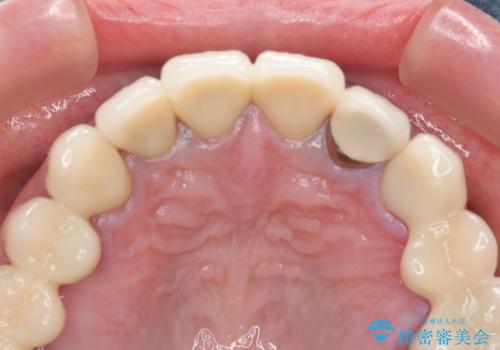

保険適応 硬質レジン前装冠から審美的でオールセラミッククラウンへ

- 変色の進んでしまった前歯を審美的なセラミック治療にしたい、と希望され来院されました。

10数年前に治療を行った保険適応の硬質レジン前装冠は変色劣化が進み、審美的に問題があるだけでなく虫歯のリスクも高くなり好ましくない状況です。

審美的かつ精度の高いセラミック治療を行うことで、汚れがつきにくく虫歯や歯周病の感染リスクを将来にわたって抑える治療が可能になります。

- 39.6万円(ジルコニアクラウン×3・仮歯×3)費用は治療当時の料金となります